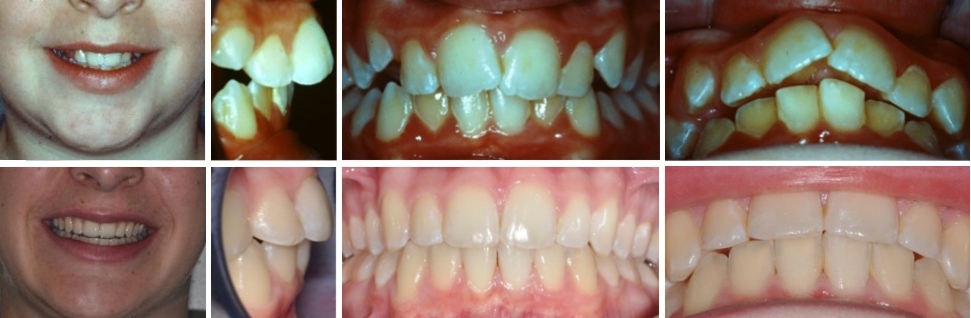

Fall 2: Offener Biss und Engstände

Therapie: Vollfixe Spange und Chirurgie